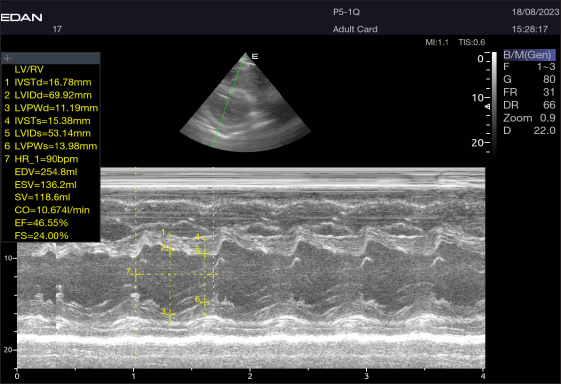

Fig. 2. Short-axis plane M mode (Mushroom shape) of a 16-year-old racing girl camel at level papillary muscle showing left ventricular dimensions (systole and diastole). IVSTd=intraventricular septal wall thickness end-diastolic, LVPWd=left ventricle posterior wall thickness end-diastolic, LVIDd=left ventricular internal dimension, LVIDs=left ventricular internal dimension end-systolic, LVPWs=left ventricle posterior wall thickness, IVSTs=intraventricular septal wall thickness end-systolic, HR=heart rate, EDV=end-diastolic volume, ESV=end-systolic volume, CO=cardiac output, EV=ejection fraction, SV=stroke volume, FS=fractional shortening.

By positioning the probe perpendicularly in the fourth intercostal space or longitudinally in the fifth space with a little clockwise rotation, the interventricular septum, ventricles, and atria could be observed in the caudal long-axis four-chamber view (Fig. 1). From this vantage point, all camels could be seen to have a left ventricle, mitral valve, interventricular septum, right ventricle, and tricuspid valve. Figure 2 shows that in the short-axis image of the cardiac ventricles obtained with a little clockwise rotation at the 4th ICS, only the right ventricle, interventricular septum, and left ventricle were visible. Here, the dimensions of all camel heart were measured in M mode. The right parasternal two-dimensional short-axis pictures of the heart’s base in the first frame were used to determine the LA/Ao ratio, by applying 2D and M mode (Figs. 3 and 4). Despite some difficulties, we successfully acquired a pulmonary image by attempting to acquire the right ventricular outflow tract for the right short axis at the level of the great vessels.

Echocardiography